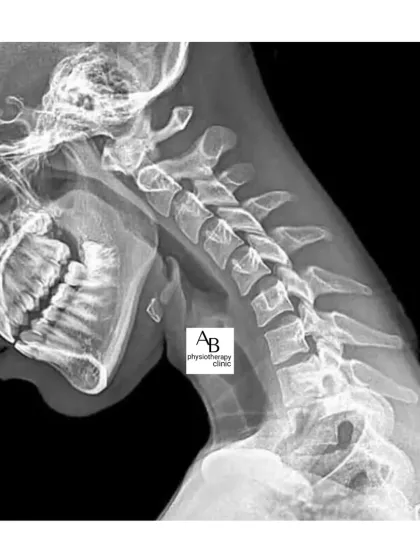

Neck, Shoulder & Posture Correction

In today's world of desks and devices, neck pain, shoulder stiffness, and poor posture are rampant. We treat everything from "text neck" and frozen shoulder to general postural imbalances, helping you stand taller and live without that nagging ache.